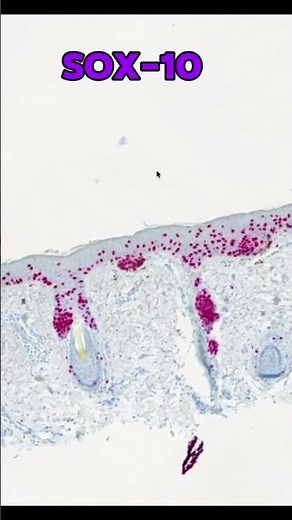

Page in Writing - Toker Cells Jared

Gardner